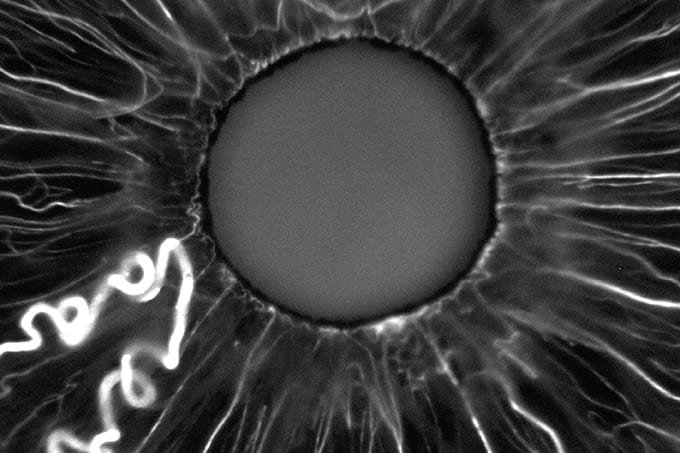

Anomalous iris vessel

Image of the Month